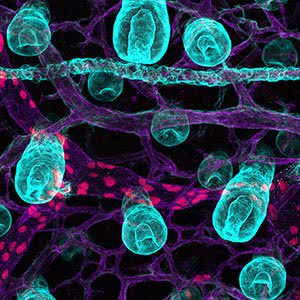

Hairy worms

Dr Genevieve Secker

Centre for Cancer Biology